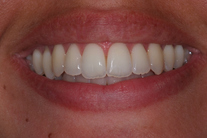

Ung kvinna som tidigare haft tandreglering. Upplever inte att tänderna står i en fin tandbåge. 11 månaders behandling med genomskinliga Invisalignskenor resulterade i ett fint leende.